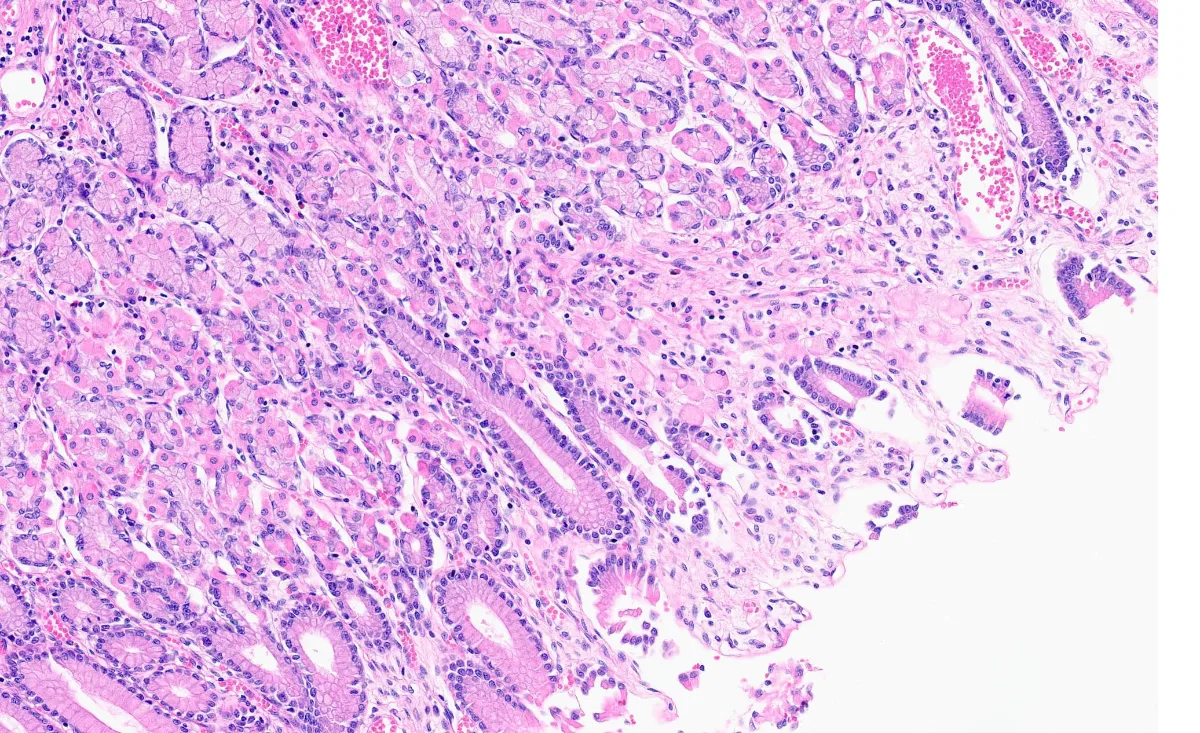

- El carcinoma gástrico difuso de células en anillo de sello se define como un carcinoma poco cohesivo compuesto predominantemente de células tumorales con mucina citoplasmática prominente y un núcleo en forma de media luna desplazado excéntricamente (PMID: 35618879).

- El síndrome de cáncer gástrico difuso hereditario (HDGC), puede presentarse con variantes patogénicas de la línea germinal CDH1, desarrollando un adenocarcinoma gástrico a lo largo de su vida en el 30-40% de los casos (PMID: 37707375).

- La mayoría de individuos con estas mutaciones, presentan adenocarcinomas intramucosos multifocales en estadio IA ocultos, a pesar de la penetrancia incompleta del cáncer gástrico avanzado asociado a CDH1 (PMID: 37707375).

- Dada la dificultad en la identificación de células, existen protocolos específicos y una lista de verificación para el examen histológico, que optimizan el aislamiento e identificación de células asociadas al carcinoma de células en anillo de sello (PMID: 37925632).

- La tinción inmunohistoquímica con E-cadherina suele mostrar una pérdida o reducción de su expresión en este tipo de tumores. (PMID: 36652613).